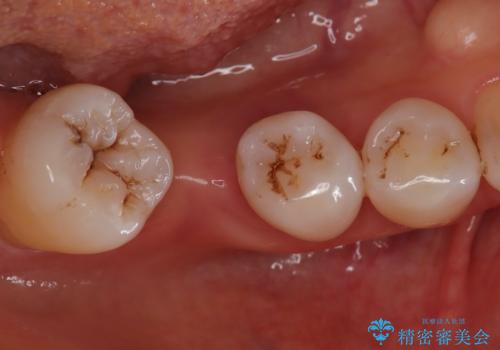

奥歯に虫歯があると言われた セラミッククラウンでキレイで長持ちする歯へ

担当医 榊原康平